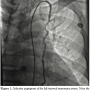

The utilization of internal thoracic arteries for coronary revascularization is well established and preferred to ensure prolonged graft patency. We report a case of a 55-year-old male who had undergone coronary artery bypass graft surgery (CABG) using only venous grafts to the left anterior descending (LAD) and first diagonal coronary arteries. The left internal mammary artery (LIMA) was not used due to extensive collateral formation from the left internal thoracic via superior and inferior epigastric arteries to the left femoral artery compensates the chronically occluded left common and external iliac arteries. Selective angiogram of the LIMA demonstrated it to be larger than normal (5 mm). The caliber is considerably larger than usual (≥3 mm). Further interrogation demonstrated it to be collaterals to the left common femoral artery via the epigastric arteries.

Imaging of the right coronary and circumflex arteries revealed no significant lesion. The left ventricular ejection fraction was normal. The injection into the LIMA showed marked increased diameter (Figure 1) with unusually long collaterals extending to the left common femoral artery (Figure 2). There was a total occlusion of the left common femoral artery (Figure 3) with reconstitution of the common femoral artery from the LIMA collaterals (Figure 4). There was no evidence of coarctation in the proximal ascending aorta identified of the aorta on this or prior coronary angiography studies (Figure 5).

In our case the unusual caliber (5 mm) of the LIMA and its collateralization of the left common femoral artery via the epigastric artery pathway is worth documentation. This condition may be rare, but it is important to realize that such an unusual collateral pathway may be present in cases in which ordinary abdominal aortography and pelvic runoff does not reveal any obvious collaterals compensating an occluded iliac artery.